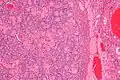

| Micrograph of a sex cord tumour with annular tubules. H&E stain. | |

It has a distinctive appearance under the microscope, from which it derives its name.

Intermediate magnification -